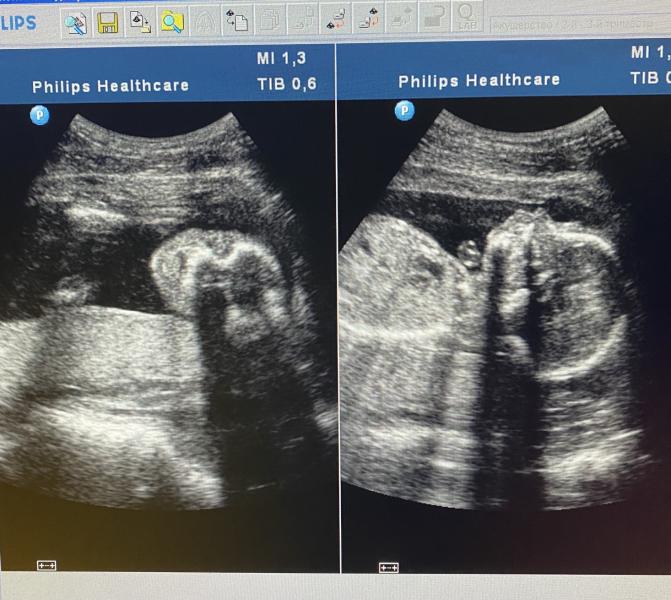

Итак, второй скрининг пройден. Шейка после эксперимента с отменой утрика и потерей сантиметра, вернулась к норме, 41 мм. Воды тоже в норме. Задняя стенка плаценты толстовата, но не критично. В дневном стационаре жк выдали дипиридамол и выписали свечи для иммунитета.

В целом все хорошо, по сроку мы идём с опережением на полторы недельки и весом 400 грамм.

Парниша смешной, все пытался палец в рот засунуть и за щечки себя держал😂

Записали мне видео немного и фото, но только на телефон дали снять (издержки омс🤷♀️). Хотя на каждом Узи или цервикометрии в поликлинике, у меня интересуются сказать ли нам пол😂 Сделали платно допплер, по сосудам все хорошо.